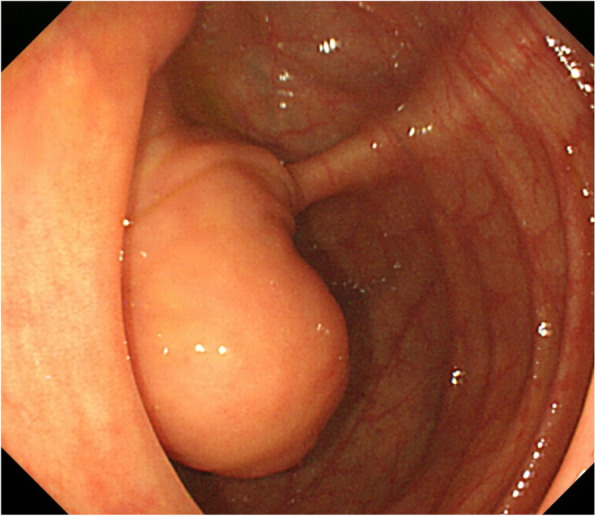

SMT with a 20-mm diameter was noted in the cecum on colonoscopy. A boring biopsy was performed after resection of the mucosa using a snare, but a tumorous lesion was not observed (Fig. 2).

Fig. 2.

SMT with a 20-mm diameter was noted in the cecum on colonoscopy